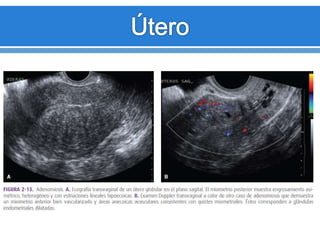

Adenomiosis

 Aumento del tamaño difuso del útero con un contorno

normal.

 Engrosamiento del miometrio posterior.

 Área afectada ligeramente mas hipoecogénica.

• 55.

Adenomiosis  Aumento deltamaño difuso del útero con un contorno normal.  Engrosamiento del miometrio posterior.  Área afectada ligeramente mas hipoecogénica.